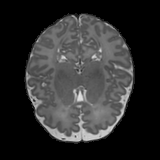

Real-world settings often do not allow acquisition of high-resolution volumetric images for accurate morphological assessment and diagnostic. In clinical practice it is frequently common to acquire only sparse data (e.g. individual slices) for initial diagnostic decision making. Thereby, physicians rely on their prior knowledge (or mental maps) of the human anatomy to extrapolate the underlying 3D information. Accurate mental maps require years of anatomy training, which in the first instance relies on normative learning, i.e. excluding pathology. In this paper, we leverage Bayesian Deep Learning and environment mapping to generate full volumetric anatomy representations from none to a small, sparse set of slices. We evaluate proof of concept implementations based on Generative Query Networks (GQN) and Conditional BRUNO using abdominal CT and brain MRI as well as in a clinical application involving sparse, motion-corrupted MR acquisition for fetal imaging. Our approach allows to reconstruct 3D volumes from 1 to 4 tomographic slices, with a SSIM of 0.7+ and cross-correlation of 0.8+ compared to the 3D ground truth.